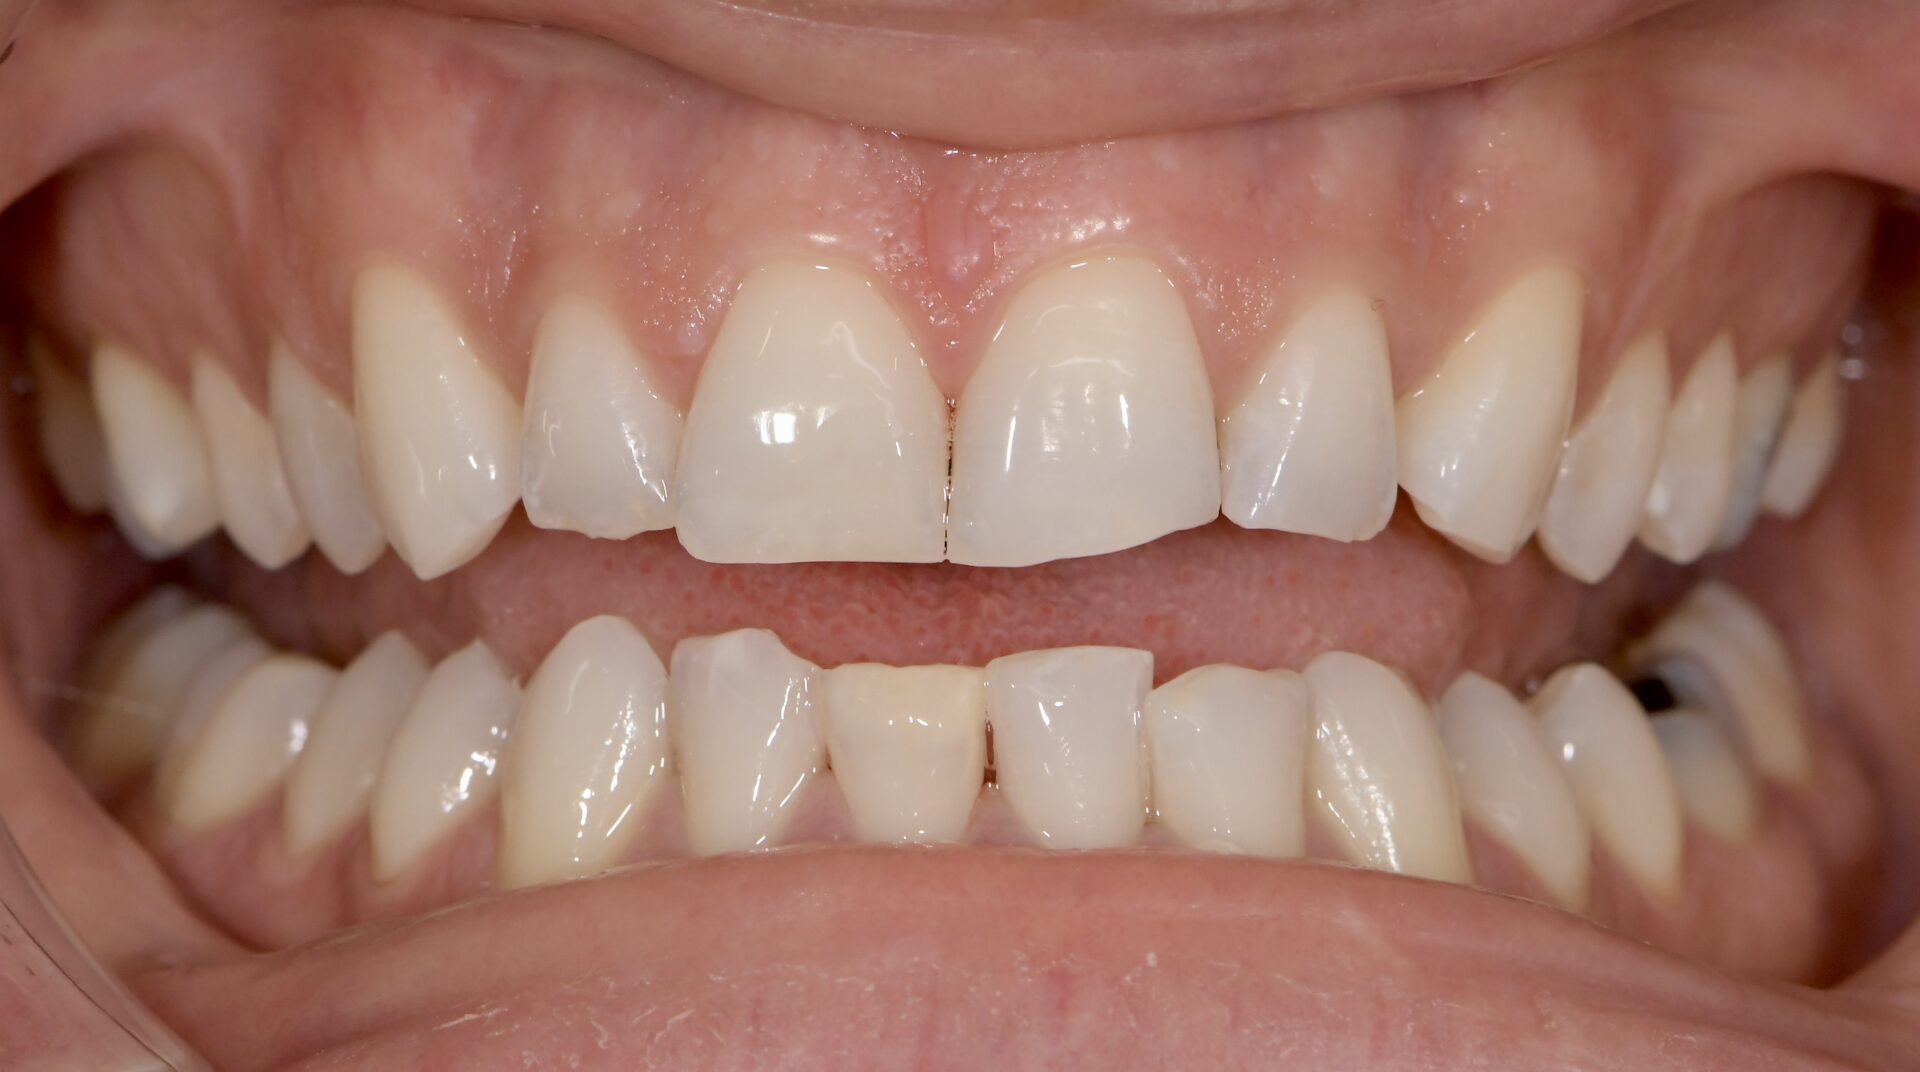

Si en antérieur, le préjudice esthétique n’est pas trop important et qu’il n’y a pas de perte de substance, il est conseillé d’attendre la majorité afin de réaliser un éclaircissement suivi de la technique d’érosion infiltration (ICON), plus ou moins une stratification de composite esthétique (Figures 8-9-10).

formation dentaire pédodontie Figure 9.

Figures 8-9-10 : Traitement antérieur, éclaicissemet bouche complète, ICON et stratification de

composite sur 11 (l’éclaircissement ayant suffit pour la 41)